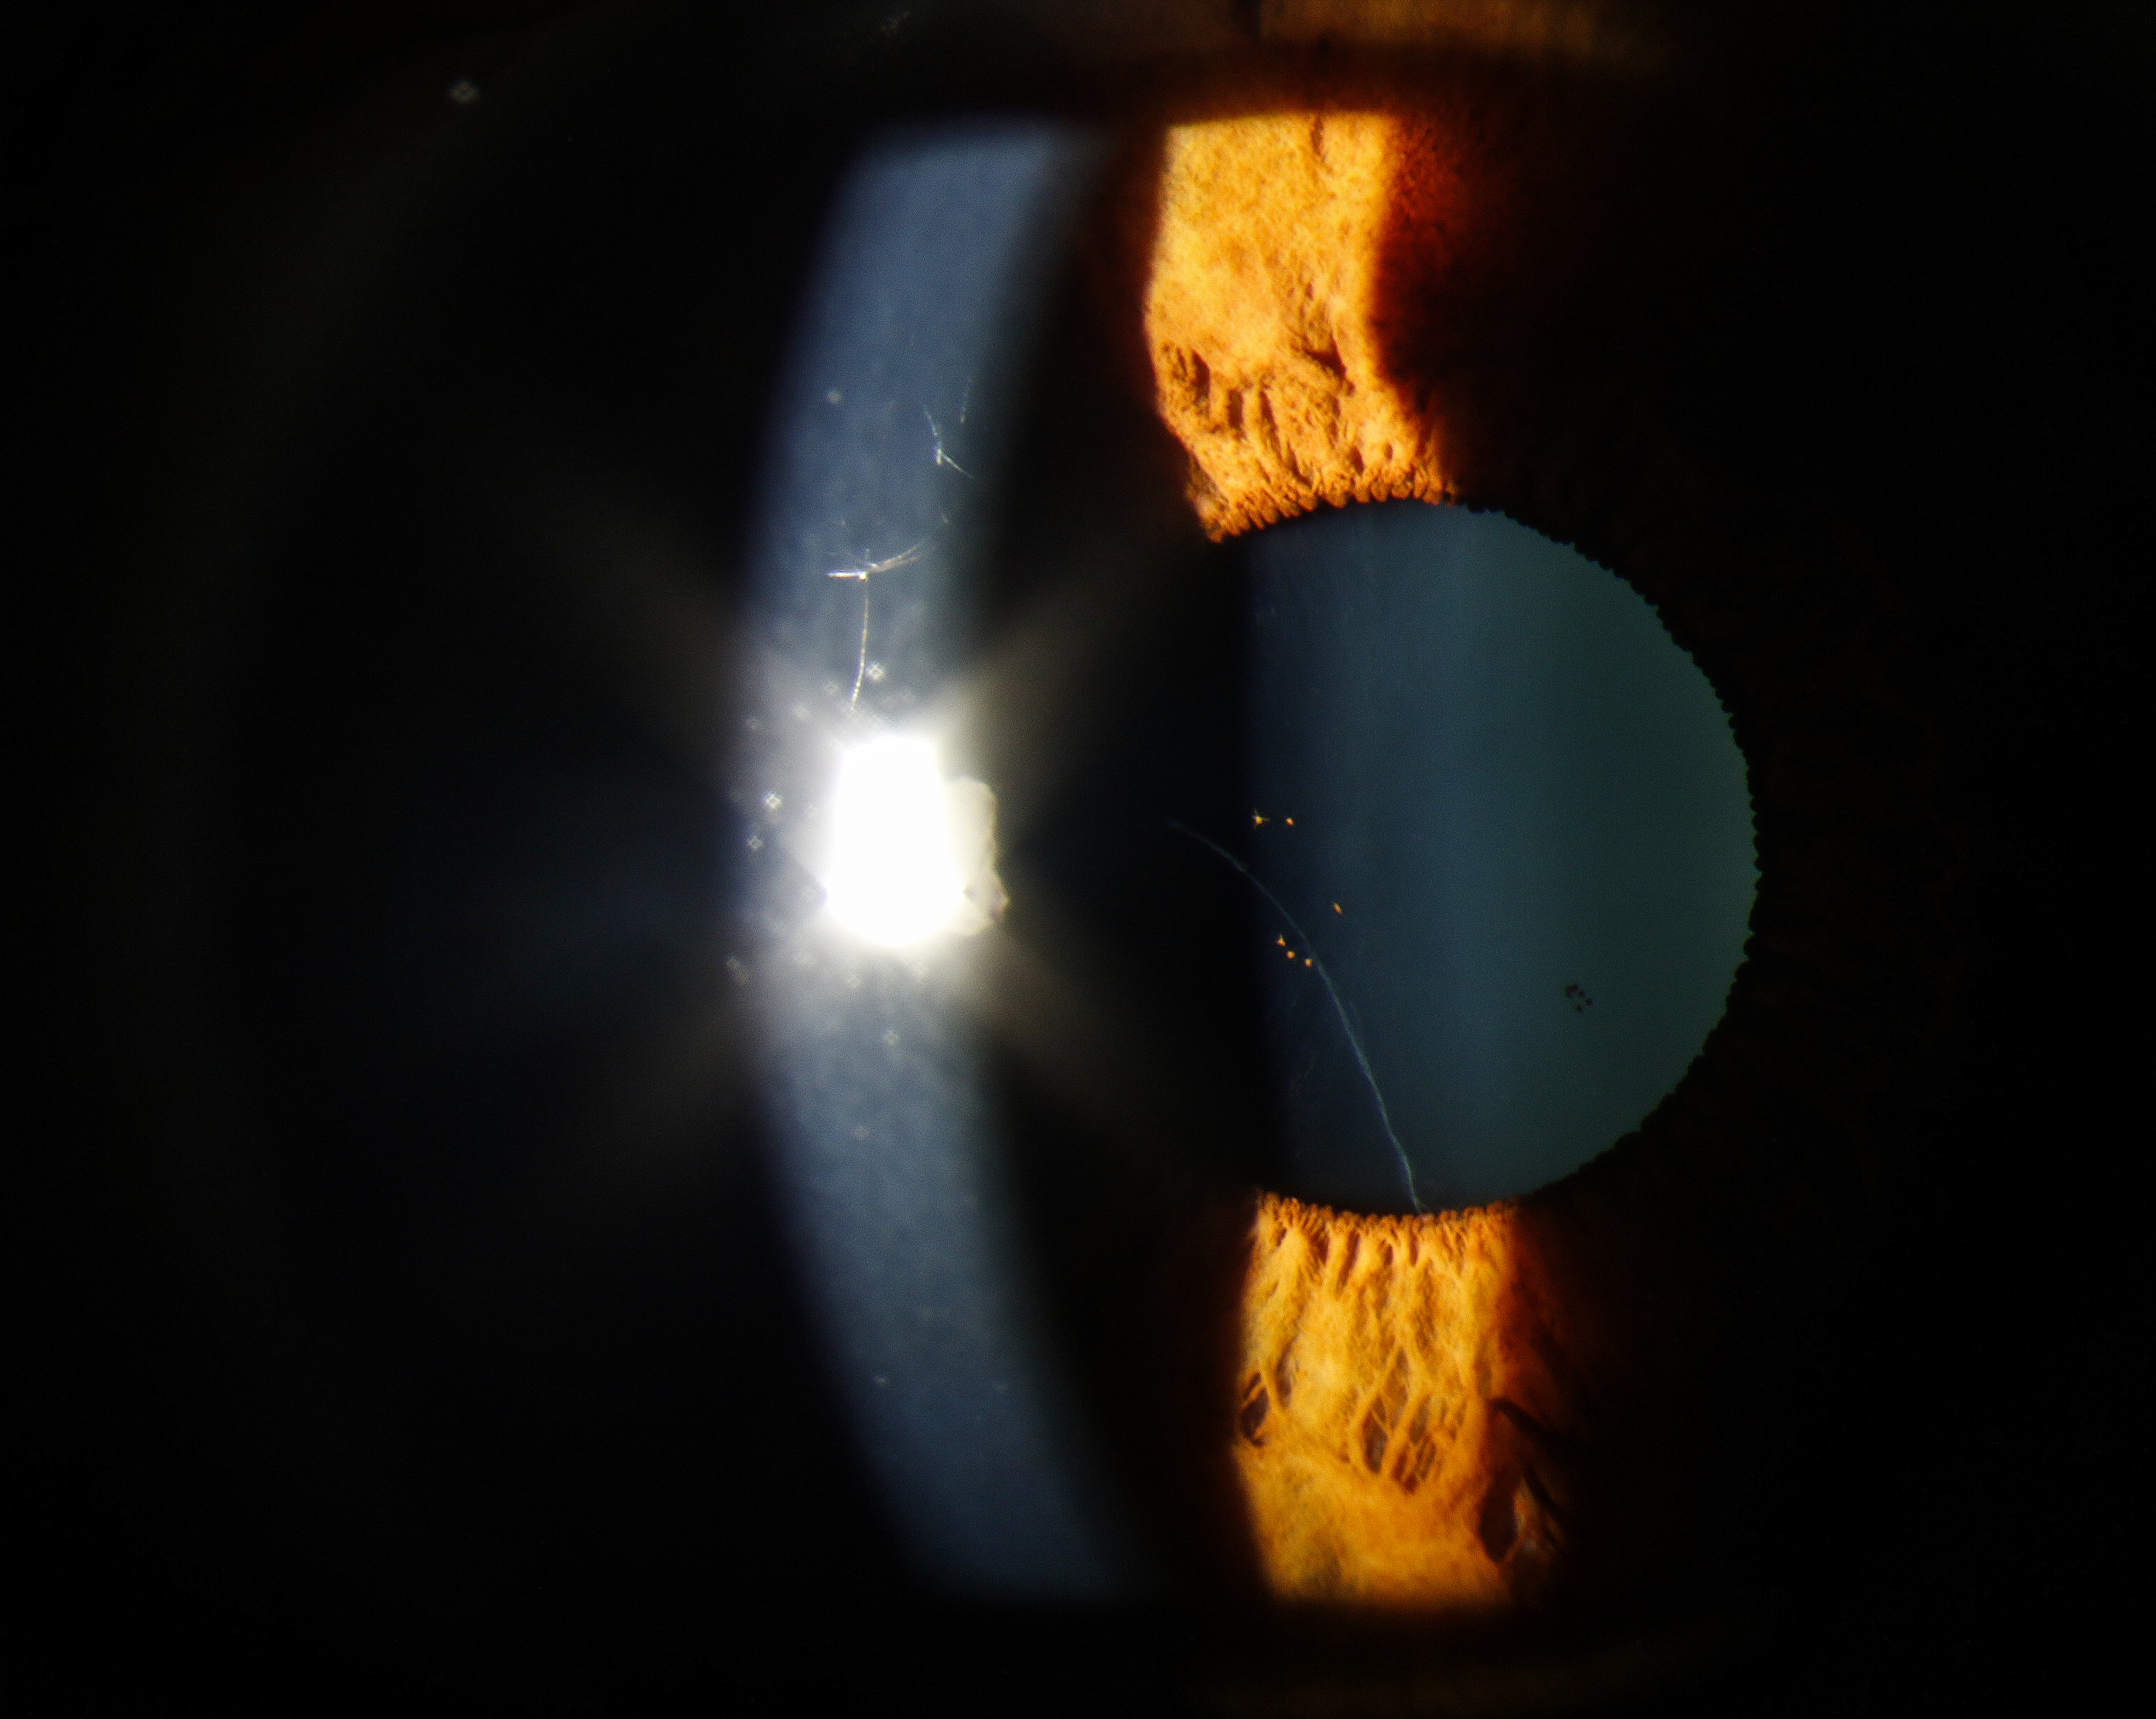

Ophthalmology